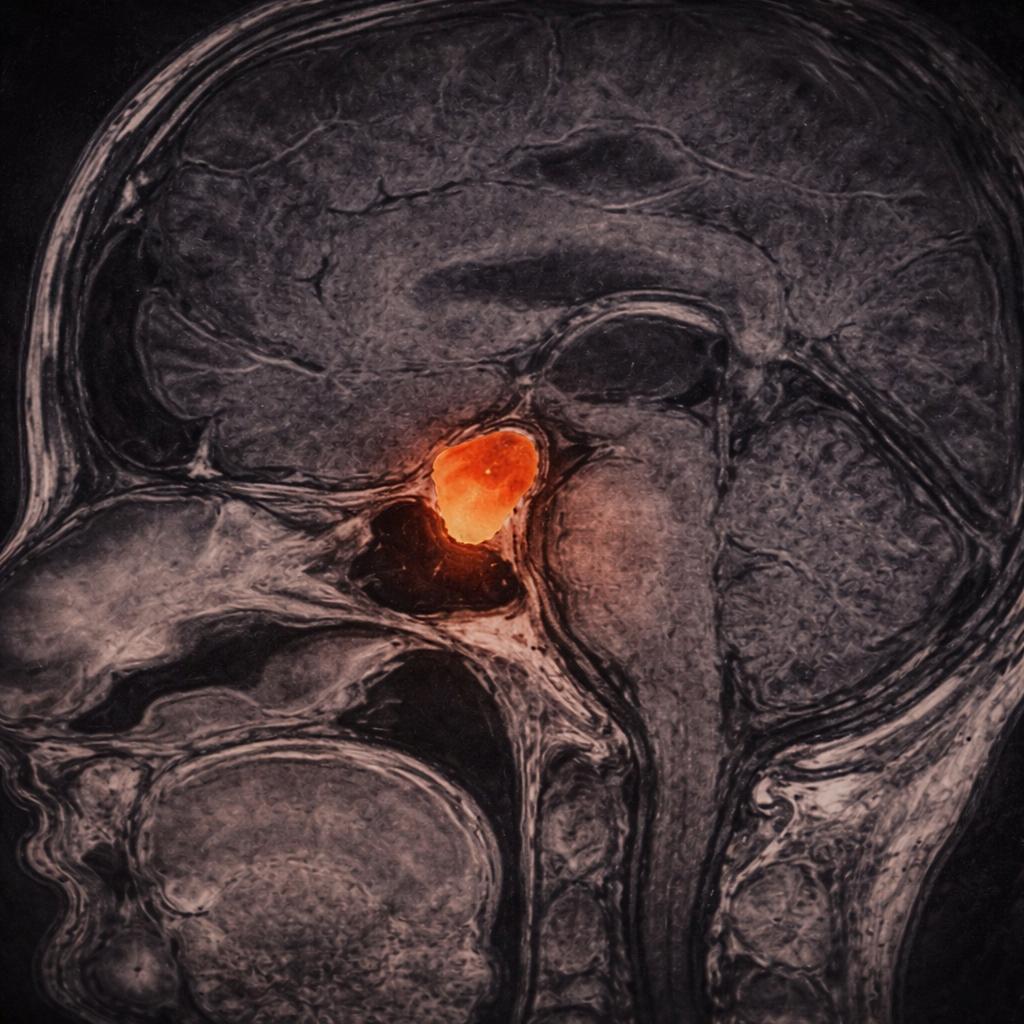

Los adenomas hipofisarios son tumores generalmente benignos localizados en la silla turca, aunque puede haber tumores invasores que se extienden más allá y dificultan su tratamiento.

La silla turca es una estructura ósea que aloja la glándula hipófisis y que, como su nombre lo indica, cuando es vista lateralmente, asemeja una silla de montar. La importancia de esta estructura radica en su cercanía con estructuras neurovasculares. Esta relación es crucial, ya que el crecimiento de un tumor hipofisiario causa frecuentemente la compresión de los nervios ópticos y produce un defecto visual caracterizado por la pérdida de la visión periférica. En algunos casos, el crecimiento de estos tumores puede invadir el seno cavernoso y los nervios que permiten la movilidad de los ojos.

El diagnóstico de los tumores hipofisarios se hace mediante una resonancia magnética cerebral/hipófisis con medio de contraste intravenoso (gadolinio).

Existen microadenomas (menores a 1 cm) y macroadenomas (mayores a 1 cm). La estrecha relación con estructuras neurovasculares es muy importante para determinar la posición de los tumores pituitarios.

Los macroadenomas tienen mayor posibilidad de desplazar los nervios ópticos y producir síntomas en el paciente.